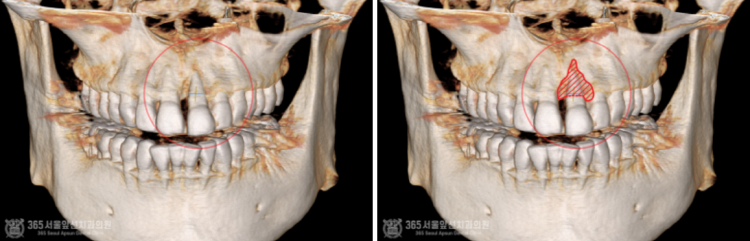

촬영일시 : 2024.07.02. 풍치로 인한 염증 부위를 색상으로 표시해보았습니다. (노란색) 3차원 CT를 이용하여 분석해보니 잇몸뼈가 염증으로 인해 녹은 상태로 매우 심각했습니다.....ㅠㅠ 촬영일시 : 2024.07.02. 결국 해당 치아는 발치를 하게 되었고, 임플란트 식립과 동시에 염증으로 인해 없어진 뼈를 재건하는 골이식을 시행하게 되었습니다. 발치를 하고 나서 임플란트 식립 및 골이식 수술 전 확인해보니 염증으로 소실된 뼈가 상당합니다. 촬영일시 : 2024.07.02. 임플란트를 식립했고 그 위로 두툼하게 골이식을 시행합니다. 일반적으로 골이식은 흡수되는 양이 상당합니다. 그래서 앞니 부위와 같이 미적으로 중요한 부위에서는 자연스러운 잇몸의 볼륨을 위해서 흡수되는 양을 감안하여 많은 양의 골이식을 시행하고있습니다. 임플란트를 식립 후에는 보통 작은 임시틀니를 드리고 그걸 사용하시는 경우가 많은데요. 지금처럼 골이식이 많이 들어간 경우에는 임시틀니를 사용할 경우 이식한 뼈가 제대로 성숙되지 못하는 경우가 많기에 다른 방식의 임시치아를 해드리고 있습니다. 위 환자분께서도 붙이는 형태의 임시치아를 해드렸고 잘사용하셨습니다. 촬영일시 : 2024.11.01. 4개월이 지나서 임플란트가 뼈와 잘 결합되었구요. 이식한 뼈도 단단해졌기에 슬슬 본 뜰 준비를 해봅니다. 동그랗게 회색 단추가 달려있는데요. 치유지대주라고 부르는 구조물로 이걸 이용하여 본을 뜨게 됩니다. 촬영일시 : 2024.11.05. 완성된 최종 보철물입니다. 사실 중간에 임플란트와 연결된 임시치아를 사용하여 잇몸 모양을 잡아주는 과정을 거쳤는데요. 아쉽게도 해당 과정에 대한 사진이 없군요 ㅠㅠ 이렇게 섬세하고 복잡한 과정을 거쳐서 임플란트 치료가 마무리 되었습니다 ㅎㅎ 이식된 뼈 부위도 통통하게 뼈가 잘되어있습니다 ㅎㅎ 만족스럽습니다. 촬영일시 : 2024.11.05. 치료가 마무리 된 후 엑스레이 사진입니다. 최종 보철물 장착 완료까지 자연스럽게 잘 마무리되어 기분이 좋네요. 직원분께서 가족의 치료를 믿고 맡겨주셨고, 그에 보답할 수 있어 기분 좋은 치료 증례였습니다. 앞으로도 더 유익한 치료 증례로 찾아뵙겠습니다. 도화역치과 365서울앞선치과의원이었습니다. 감사합니다. [ 치료기간: 2024년 7월2일 ~ 2024년 11월 5일 ] ※ 365서울앞선치과의원의 모든 포스팅은 각 진료과 의료진이 직접 작성합니다. 365서울앞선치과의원 블로그의 임상 케이스 게시물은 환자분께 의학적으로 정확하고 상세한 정보를 드리기 위해 각 진료과 의료진이 직접 작성하며, 모든 증례 사진은 본원 의료진이 직접 시술한 증례를 촬영한 것으로, 의료법 제23조, 제56조에 의거하며 환자분의 동의를 얻어 포스팅에 사용하였습니다. 또한 해당 케이스는 본 환자분의 치료 결과이며, 환자 상태에 따라 치료의 결과는 달라질 수 있습니다. |